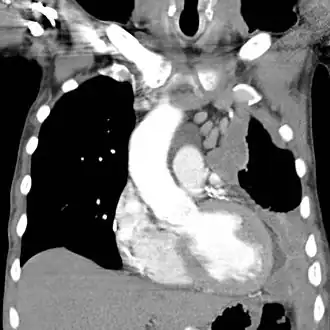

CT-scan van een mesothelioom links in de thorax uitgaande van het longvlies. (rechts op de afbeelding)